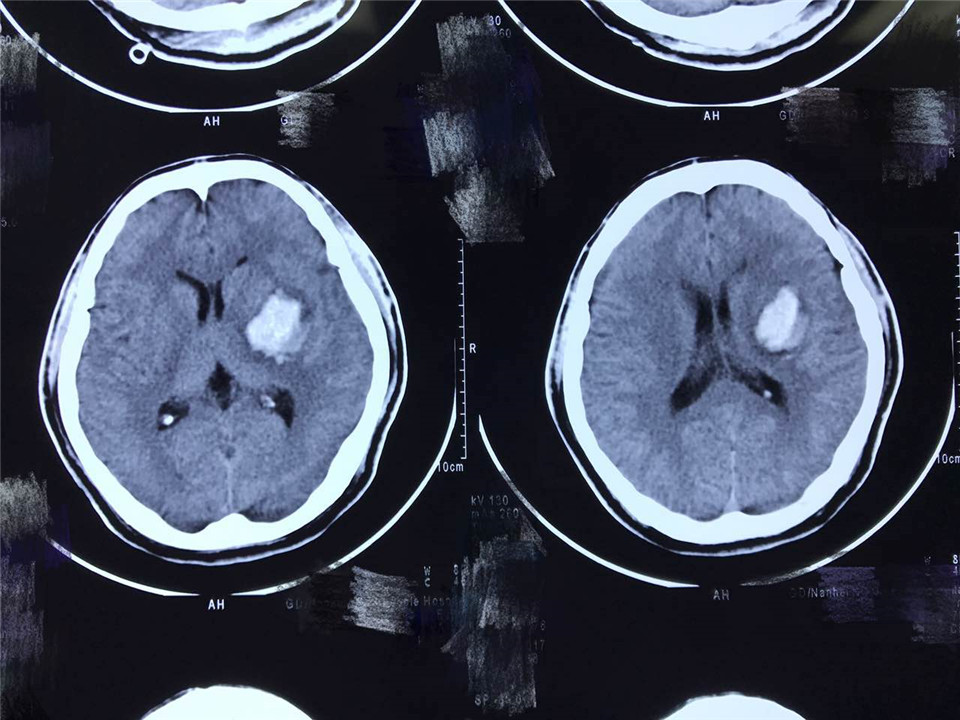

现病史:患者于2017年5月4日外出购物时突然出现右侧肢体乏力,言语不清,口角歪斜,当时神清,无恶心呕吐,后病情逐渐加重,出现意识障碍,查头颅CT示左侧基底节区脑出血,出血量约50ml。次日转至南方医院神经外科,即于全麻下行左侧血肿腔穿刺引流+颅内压探头置入术,术程顺利,术后予控制血压、血肿引流等对症治疗后病情逐渐平稳,遗留言语不清,右侧肢体无力,吞咽障碍。为进一步中西医结合康复治疗于2017年5月21日来我院就诊,以“脑出血恢复期”收入院。入院症见:患者神志清楚,精神一般,言语不清,发音含混,口角歪斜,无流涎,右侧肢体活动障碍,右上肢不能抬举,右手不能持物,右下肢不能负重,不能独自保持坐立位,嗜睡,鼻饲全流食,4日未解大便,小便可,舌淡红,苔黄厚,脉濡。体重未见明显减轻。